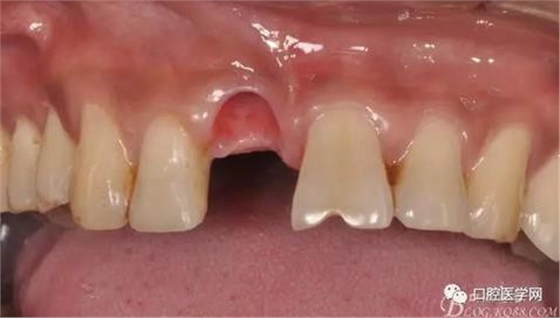

圖4 術(shù)前正位頜面照

圖9 三個(gè)月后袖口形成正位照